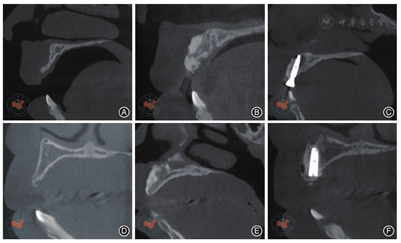

两组随访率为100%。在愈合期及随访期内50枚种植体无松动脱落,功能行使良好,患者无明显不适,种植体存留率达到100%。观察组、对照组术前及术后随访照片见图2,CBCT图像见图3。

典型病例 患者,女,22岁,因10年前外伤致右上前牙脱位一直未行修复治疗,现成年后要求种植修复。口内检查:11缺失,上前牙牙列存散在间隙,薄龈型,11对应唇侧骨凹陷。术前CBCT测量水平向骨宽度2.35 mm。完善术前检查,拟采取改良骨劈开联合GBR,植入ANKYLOS® C/X 3.5×14 mm种植体完成修复。术前常规预防性使用抗生素,常规消毒铺巾,局部浸润麻醉下于缺牙区行梯形切口,翻瓣,显露牙槽骨,超声行缺牙区两端骨切开,于牙槽嵴顶下2 mm处行骨切开达腭侧黏膜;切口呈U型,利用骨凿将骨块翘起轻轻推向唇侧,骨块呈"青枝骨折",骨块唇舌侧植入天博骨粉0.5 g,盖海奥胶原膜,无张力缝合创口。术后常规消炎,14 d后拆线,创口愈合良好。6个月后CBCT复查,测量水平向骨宽度为7.12 mm,植入ANKYLOS® C/X 3.5 × 14 mm种植体1枚,行即刻修复,6个月后完成最终修复,6个月后复查。完成修复当日及负重6个月PES值评估,修复当日及负重6个月完成边缘骨水平量测量。结果显示,行改良骨劈开联合GBR术后6个月水平向骨宽度获得了显著的骨增量,修复获得了良好的前牙美学效果,负重6个月的边缘骨吸收量较少,患者满意度高。典型病例手术术式见图4。